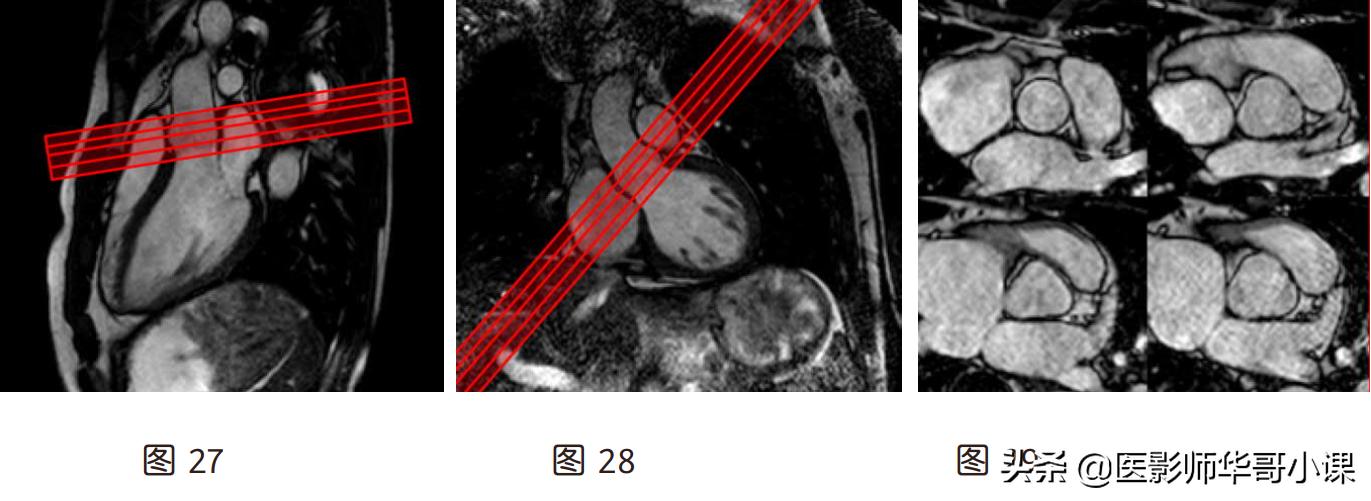

(10)主动脉瓣(图 29):在斜矢状左室流出道与斜冠状左室流出道上,垂直于升主动脉